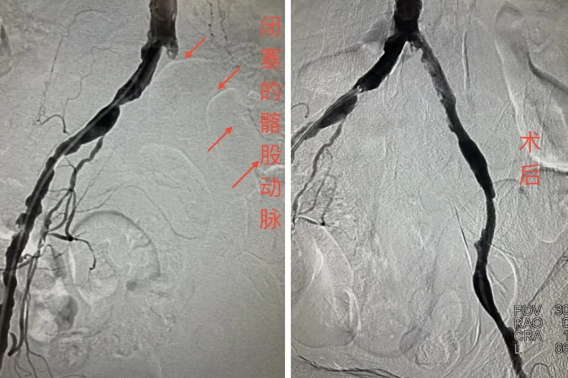

患者为老年男性,因“左下肢疼痛、麻木、无力20余天”从外院转入榆林市星元医院。入院时,患者左下肢青紫发凉、足端发灰,伴趾部溃疡,股动脉、腘动脉及足背动脉搏动均消失,ABI指数为0,急诊CTA确诊为左侧髂股动脉血栓性闭塞,Fontaine分期达3-4期,面临极高截肢风险。

面对紧急病情,介入血管科团队迅速评估,在与家属充分沟通后,果断决定实施“下肢动脉血栓机械旋切清除术”。手术中,团队凭借娴熟的介入技术与丰富的临床经验,精准操作,将堵塞血管的血栓彻底清除,闭塞血管瞬间恢复血流。术后患者左下肢疼痛立即缓解,皮温回升,血运重建良好,肢体得以成功保留。